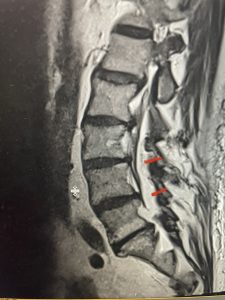

Epidural lipomatosis is a relatively rare condition where normally present fat in the epidural space is hypertrophied and can cause severe thecal sac compression. It is generally deposited more in the lateral and dorsal epidural space. This can be caused by long term steroid use and obesity, but also can be idiopathic. He had done well until more recently had developed low back pain with bilateral thigh pain and numbness. He had difficulty walking because of the pain. A new MRI (Fig 5) revealed that he had developed severe degeneration of the L1-2 segment above his prior decompression and fusion with a large extruded disc/osteophyte, right greater than left with severe thecal sac compression. He also had some residual T12-L3 residual epidural lipomatosis.

He had failed conservative treatment consisting of neurontin, physical therapy and epidural injections. He underwent revision laminectomy T12-L3 to decompress and explore prior fusion. He did have significant epidural fat encountered particularly at L1-2. The fat in epidural lipomatosis has a much more firm, globular texture. It takes a while to search within the fat, gently dissecting with a Penfield 4, to finally find the thecal sac! We encountered a large subligamentous extruded fragment lateral to the thecal sac on the right above the take off of the L2 nerve root. We removed any more residual fat at the L2-3 level and T12-L1 and decompressed the sac well. On exploration of the prior fusion it was fairly solid, but had some gaps at L2-3 fusion mass. Therefore we added a T12-L3 in situ fusion to augment those gaps and because we were at the thoracolumbar junction we extended fusion to T12. Post operatively he had relief of his leg pain.

(Figs 5a): Sagittal (a) and axial (b) T2-weighted lumbar MRI demonstrating status post lumbar decompression and insitu fusion L2-5 now well decompressed (blue dash) with development of new (red arrow) severe stenosis and with superimposed right L1-2 disc herniation (blue arrow)

(Figs 5b)